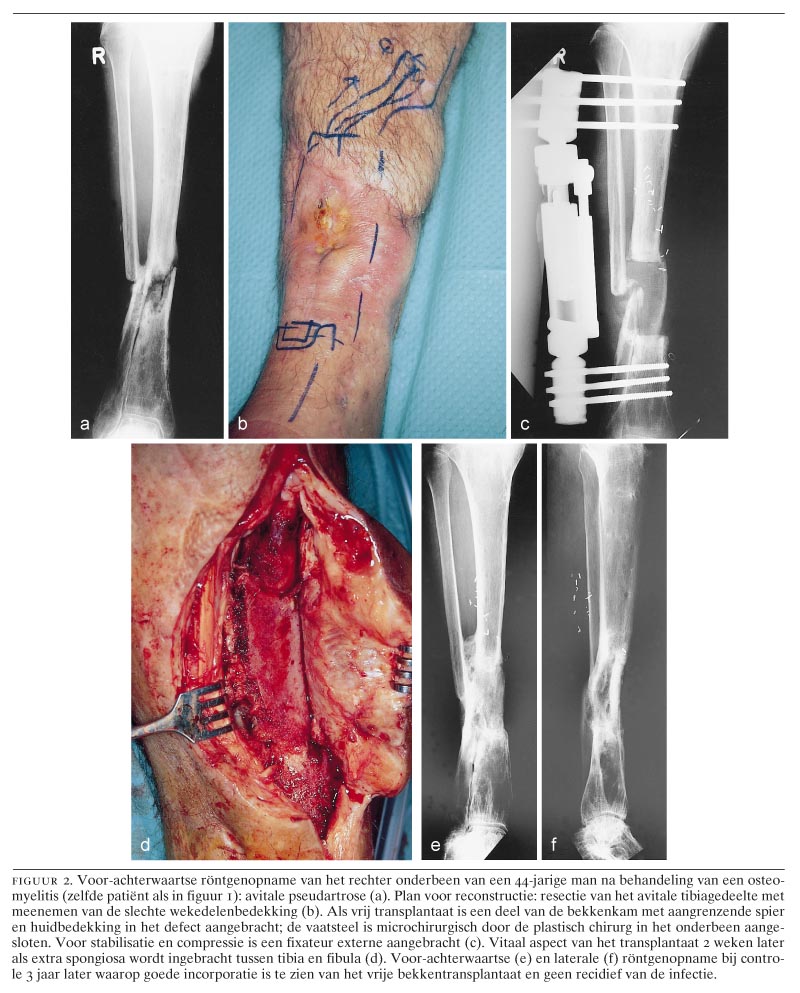

Als de infectie goed geneest, kan zo nodig daarna een reconstructie worden uitgevoerd: botdefecten maken vaak bottransplantatie, botsegmentverschuiving (Ilizarov-methode) of vrije-spierlapplastieken nodig.